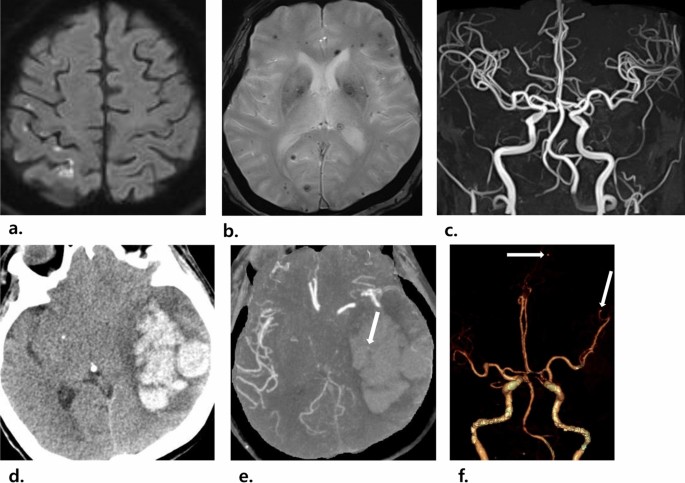

Cerebral microbleeds were detected in 57% (66 of 115) of all patients, in 66% (23 of 35) of the patients with neurological symptoms, and in 54% (43 of 80) of the patients without neurological symptoms. Of the 66 patients with microbleeds, 24 underwent follow-up brain MRI, and 10 (42%, 10 of 24) showed an increasing pattern. Microbleeds mainly showed an increasing pattern in deep/subcortical white matter or the cerebellum than in the basal ganglia or thalamus. No significant differences in microbleeds were noted between patients with and without neurological symptoms (P = 0.233, respectively). Figure 2 shows images of a patient with left-sided infective endocarditis and embolic infarctions and cerebral microbleeds.

Images of a 69-year-old woman with left-sided infective endocarditis. (a,b) Brain MRI images show multifocal, small, high-signal-intensity lesions in the right frontal and parietal lobes on the diffusion-weighted image (a), which suggests embolic infarctions, as well as multiple cerebral microbleeds in both cerebral hemispheres on the T2*-weighted image (b). (c) No definite vascular abnormality was detected on brain MR angiography. After 4 days, the patient had drowsy mentality and vomiting, and a CT scan was performed. (d) Axial non-contrast-enhanced CT imaging shows a new acute intracranial hemorrhage in the left temporoparietal lobe. (e) A small enhancing lesion (arrow in e) is seen on axial maximum-intensity projection imaging, suggesting that a infectious aneurysmal rupture caused an acute intracranial hemorrhage. (f) On the 3D volume-rendered image of CT angiography, two additional infectious aneurysms were detected in the distal branch of the left ACA and left MCA (arrows in f). Despite emergency decompressive craniectomy, the patient died.

Notably, among the 9 patients with infectious aneurysm, aneurysmal rupture occurred in 4 (44%, 4 of 9), with a median period of aneurysmal rupture of 5 days (range 4–78 days). Of these 4 patients, 2 with aneurysms detected on MR angiography were followed-up without significant neurological sequelae after clipping surgery, whereas the other 2 patients with aneurysms that were undetected on MR angiography died despite decompressive craniectomy. Figure 2 and Supplementary Fig. e-2 show images of two patients with left-sided infective endocarditis and undetected/detected infectious aneurysms on MR angiography, respectively.